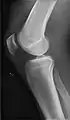

- زانو - AP و جانبی. پروجکشنهای داخلی کندیلار(Condular) در صورت درخواست.

زانوی راست، قدامی خلفی

زانوی راست، جانبی

استخوان کشکک (کمی انحراف) افق مرئی